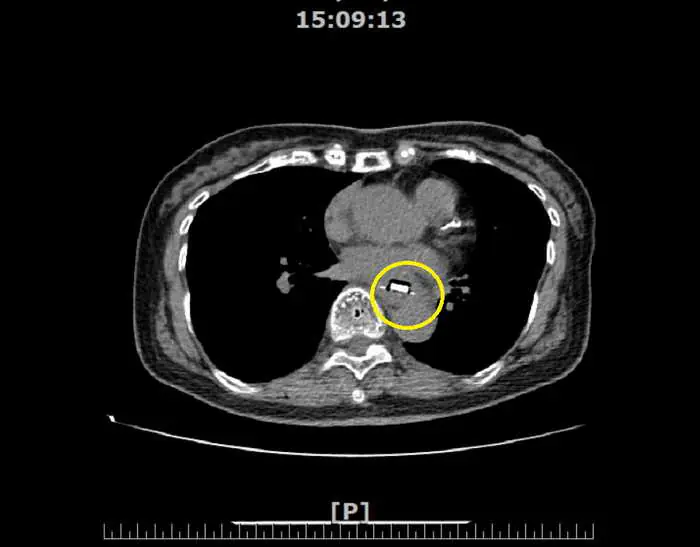

【記者張德欽、張珊瑜、張文煌、林慶文/南投報導】有部分民眾為了分裝方便,會使用剪刀將排裝的藥丸剪成一個一個小方塊的形狀,但這樣其實會增加誤食的風險。南投一名84歲蔡阿嬤日前在吞藥時,就不小心把藥丸連同其鋁箔包裝一起吞下肚,結果食道被尖銳鋁箔片哽住,造成食道潰瘍。所幸透過內視鏡順利取出異物,治療後恢復情況良好。醫師提醒誤食尖銳物可能會造成食道發炎穿孔甚至是腸穿孔的危險,建議若不慎吞入異物,喝水後仍異物感明顯未達緩解,則建議就醫接受檢查治療。

84歲蔡阿嬤在家人陪同下,至衛生福利部南投醫院洪弘昌院長的肝膽腸胃科門診就診,阿嬤向院長表示自己的喉嚨痛了一個禮拜,且總是卡卡的,有明顯異物感。洪弘昌院長細心問診下,得知阿嬤有使用剪刀切割藥物的習慣,因為藥品的包裝材質較硬,被切割後邊緣較鋒利,懷疑老人家不慎連同包裝誤食而卡住。透過內視鏡檢查發現藥丸的鋁箔片包裝就卡在食道上,安排住院以胃鏡取出異物並且藥物治療,治療食道潰瘍及預防感染。

肝膽腸胃科黃耀光醫師表示,民眾常見誤食的異物有魚刺、雞骨頭或假牙,大部分的異物會自然排出,但少部分尺寸較大或較尖銳的異物可能會導致食道黏膜受傷甚至穿孔。穿孔可能引發縱膈腔炎或造成食道-氣管廔管或刺穿主動脈形成主動脈-食道廔管,未即時處置可能會有生命危險。黃耀光醫師表示,所幸這名患者誤吞的異物僅造成食道黏膜受傷,尚未造成穿孔等嚴重併發症。

圖文:阿嬤吃藥不慎連鋁箔包裝一起吞下 卡食道就醫透過胃鏡取出。